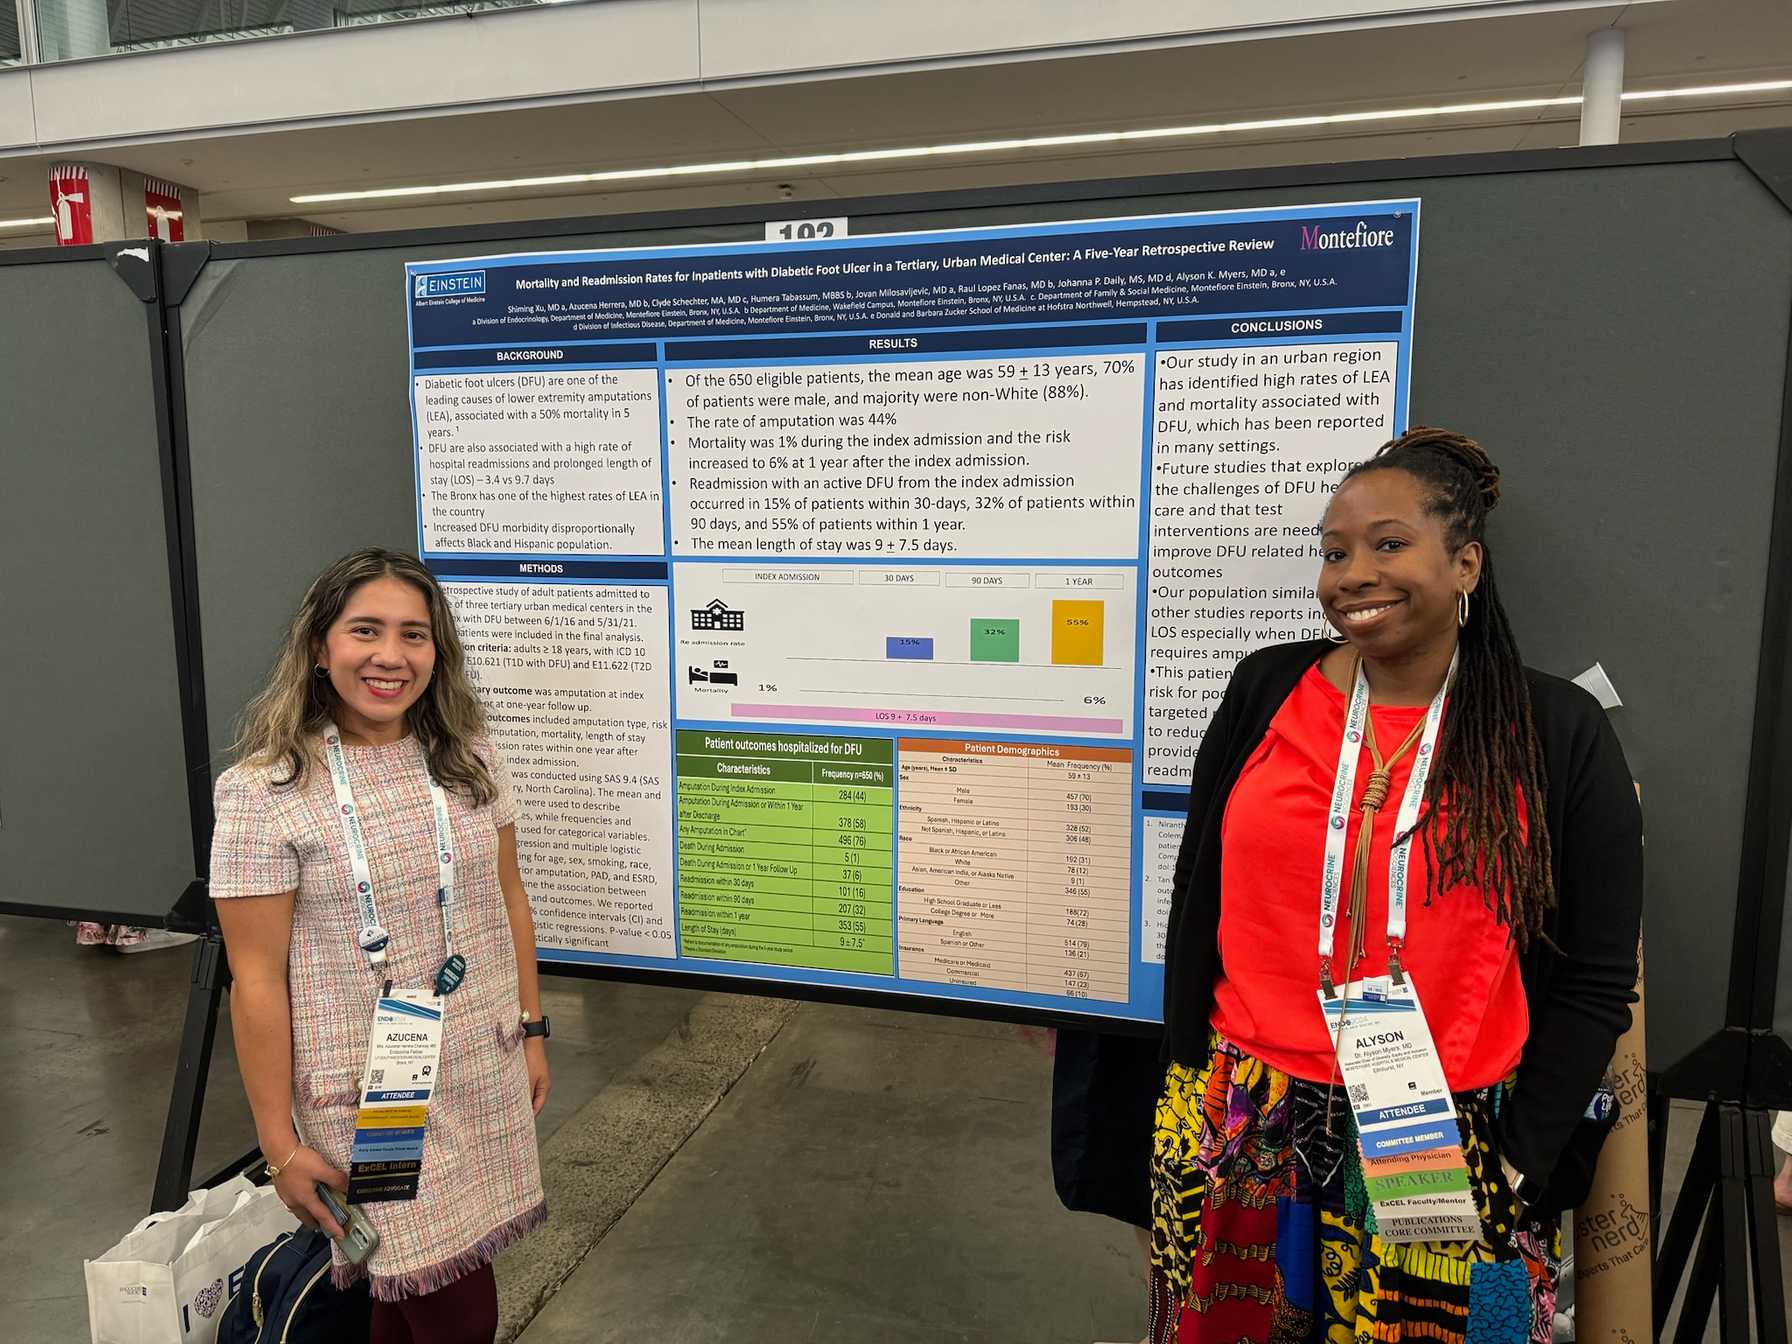

- Contribution to medical literature through the preparation of case reports, abstracts, posters and manuscripts to present in local, regional and national conferences and forums

Jacobi Medical Center (JMC) is a 457-bed municipal hospital that provides healthcare for 1.2 million people in the Bronx and the broader New York City area. One of New York City’s largest medical facilities, JMC houses the only burn unit and Level I pediatric trauma center in the Bronx. With a high volume of clinical visits and emergency room visits, JMC is an excellent location for our residents to acquire skills in acute care, trauma and intensive management. Endocrinology fellows develop experience as consultants and provide specialized care to a diverse and complex community within fellow-run clinics.

Offering rich opportunities for research

Endocrinology Fellows become familiar with research in their first year under the stewardship of Sofiya Milman, MD, Associate Program Director for Research. Depending on their experience and future career interests, fellows can choose to initiate their own research project or join an ongoing project, working with helpful and experienced mentors. Fellows also participate in didactic seminars on research methodology, scientific writing and quality improvement studies. During their training, fellows gain valuable research experience, and most contribute to their field by presenting their findings at regional or national conferences or in a manuscript.